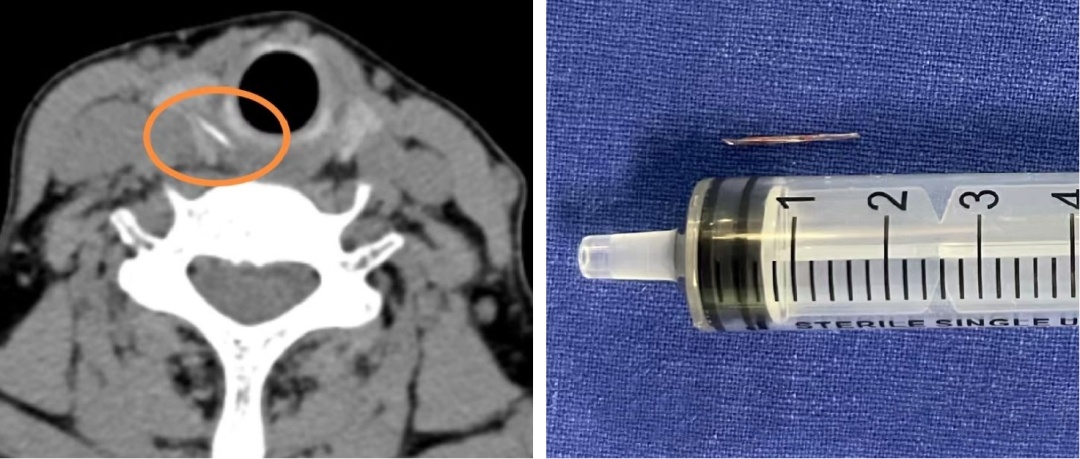

耳听为虚眼见为实,刘阿姨意识到问题的严重性,起身去了CT室。影像结果证实了之前的猜测:在右侧甲状腺位置,发现了一条索状的高密度异物影,极有可能是鱼刺穿透食道壁,扎进了甲状腺。

情况变得十分棘手。仅仅依靠内窥镜做微创手术,显然无法取出这根“逃逸”的鱼刺。经过审慎评估,邹文焘决定为刘阿姨实施全麻下颈侧切开术,最终成功从右侧甲状腺中,取出了一枚长约1.5厘米的鱼刺。探查还发现,周围的食道黏膜有轻度肿胀,便对创面作了仔细消毒。术后,刘阿姨喉咙的疼痛明显减轻,经过抗炎治疗,颈部的切口愈合良好。